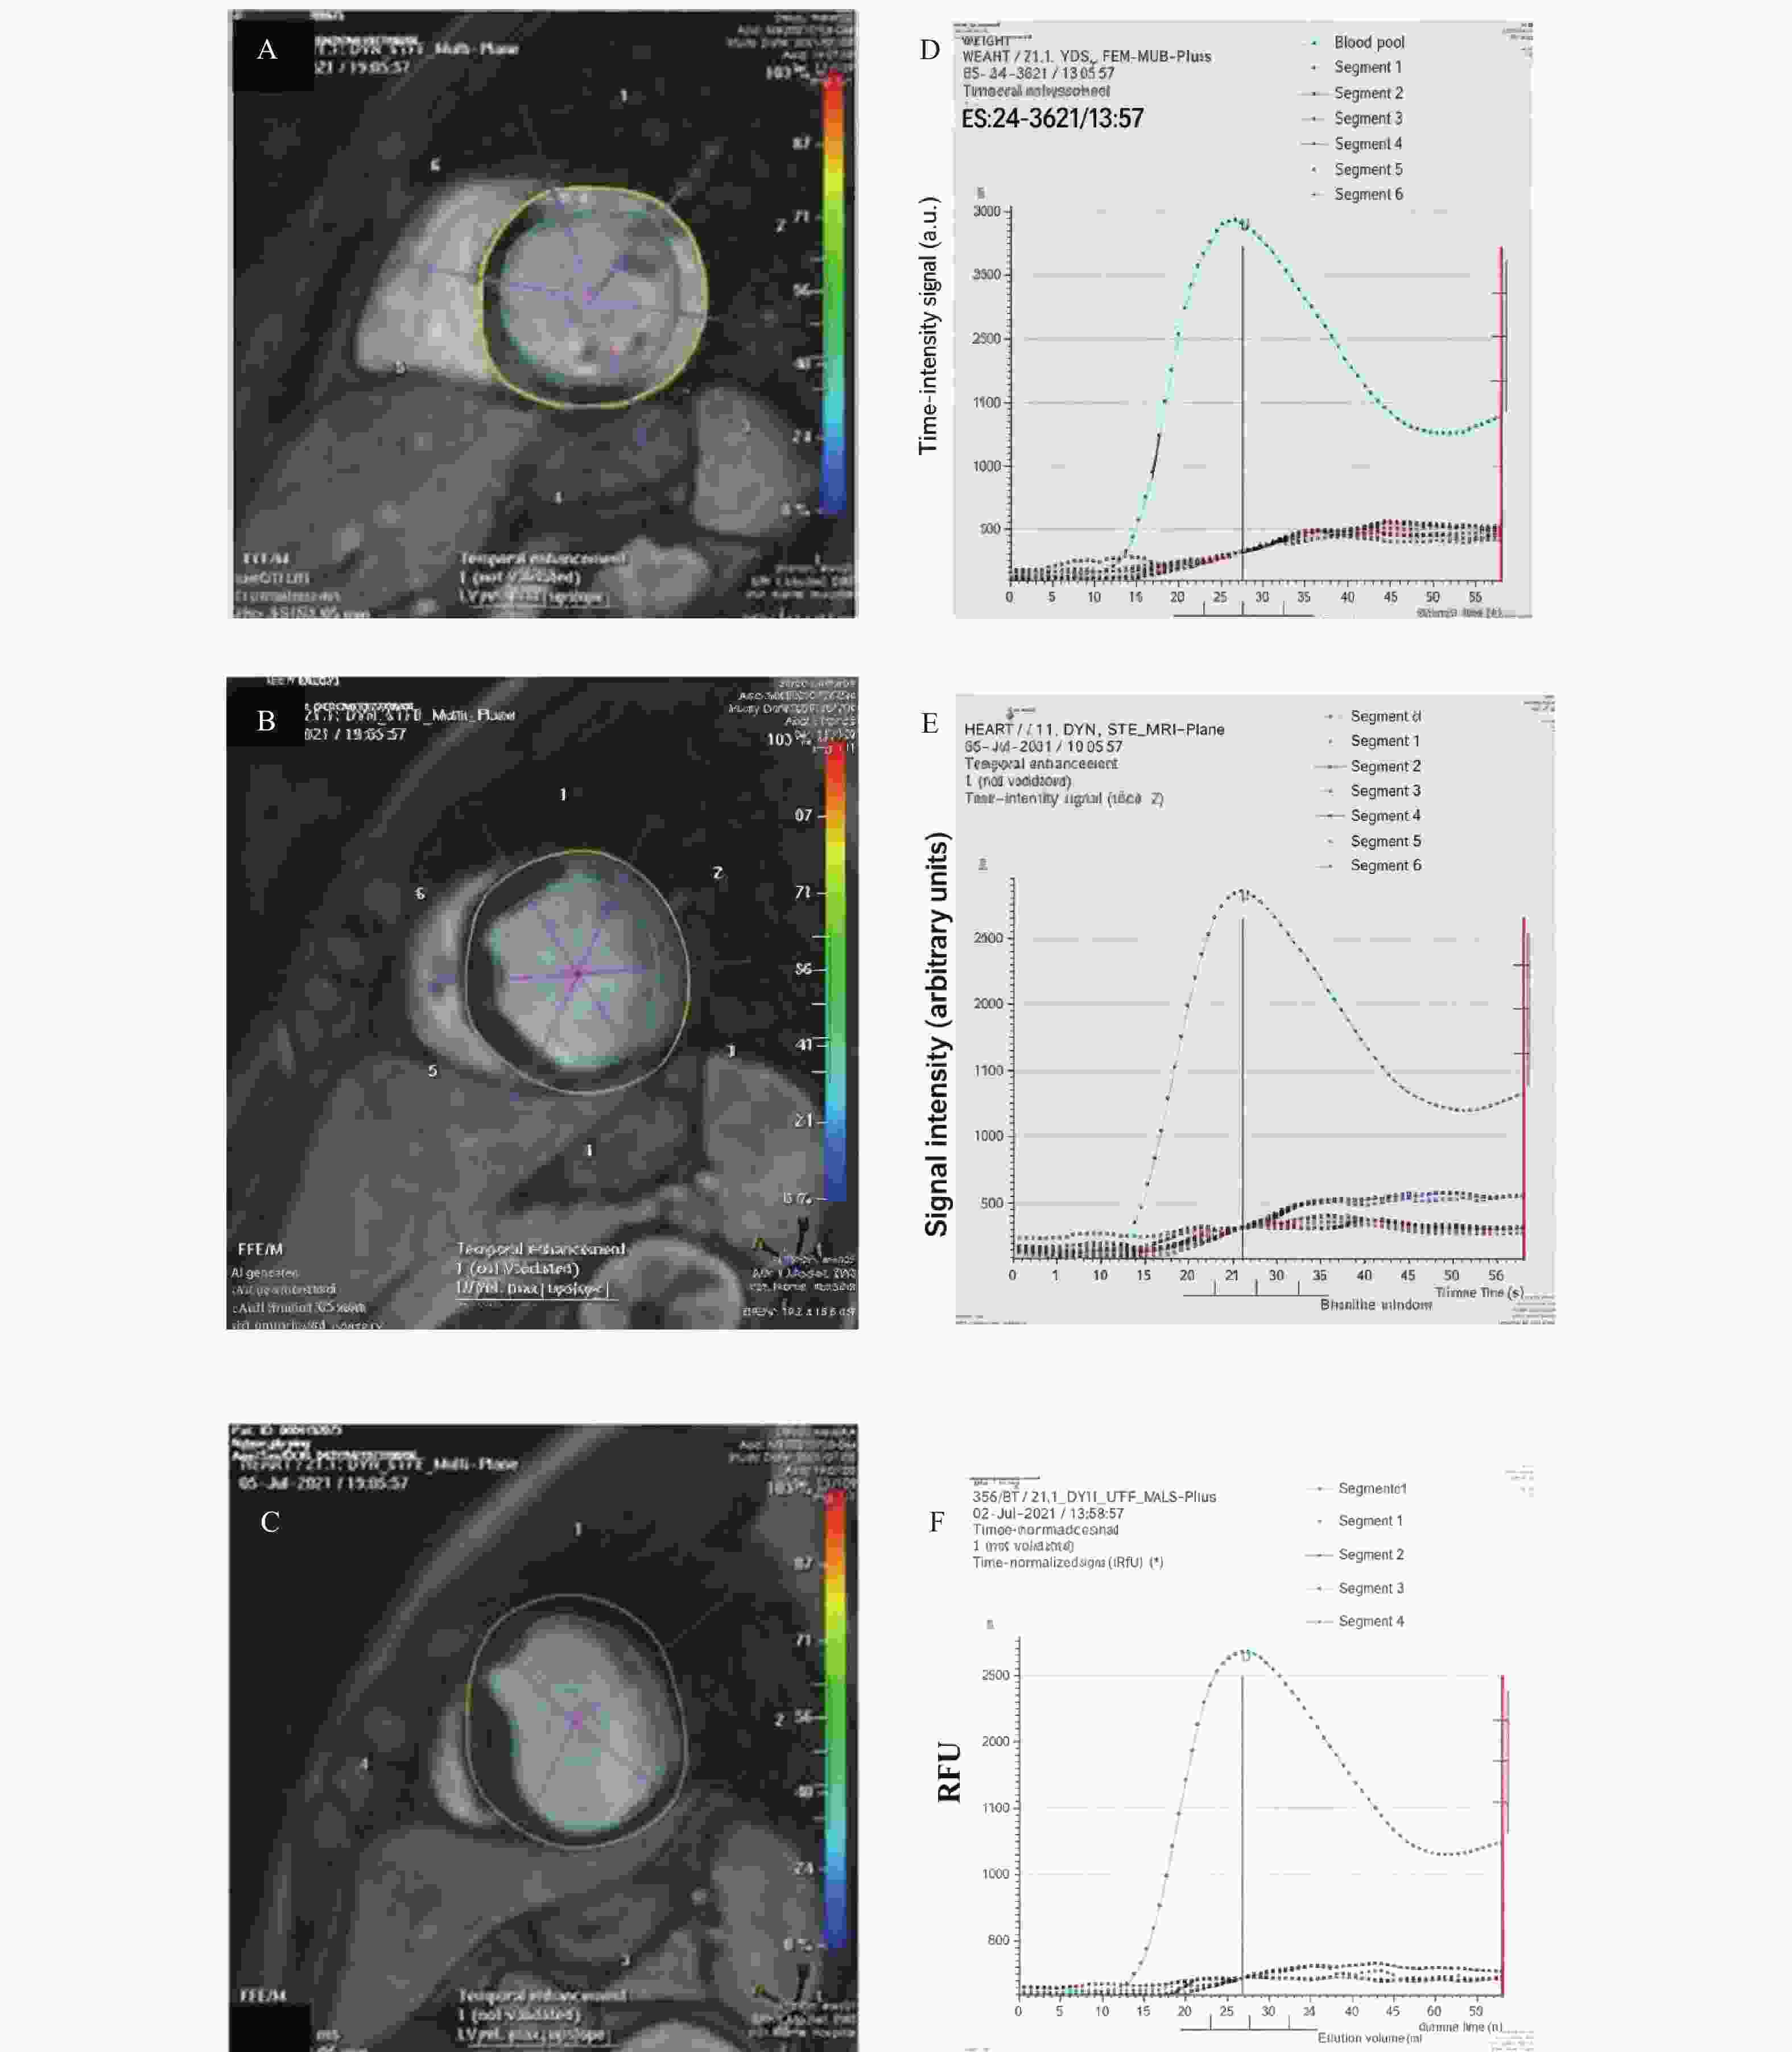

目的 通过心脏磁共振评估基于冠状动脉造影的微循环阻力指数对于冠状动脉微循环障碍的诊断效能,并进一步探究冠状动脉微循环障碍与无症状脑梗死间的相关性。 方法 选取2021年1月至2024年12月期间就诊于昆明医科大学第二附属医院心血管内科的患者231例。通过FlashAngio系统对冠状动脉造影图像左前降支血管进行分析得出caIMR值,以25为界限分为冠状动脉微循环正常组(caIMR<25,n = 126)和冠状动脉微循环障碍组(caIMR≥25,n = 105)。收集所有患者的一般临床资料、实验室指标(血常规、生化全套、糖化血红蛋白)、颅脑CT/MRI结果、心肌微循环磁共振灌注参数(达峰时间(tpeak)、相对峰值信号强度(RSIpeak)、最大上升斜率(Slopemax))、经胸超声心动图常规参数。 结果 (1)50例同时完善CMR和caIMR的患者, caIMR≥25组左前降支支配区域出现了不同程度的tpeak延长,RSIpeak和Slopemax降低,表明caIMR≥25组存在冠状动脉微循环障碍。进行Cohen's Kappa检验一致性分析, Kappa值0.839(P < 0.05),表明caIMR对于CMD的识别具有较高的准确度和评价效果;(2)127例糖尿病患者按照糖化血红蛋白(HbA1c)水平分为血糖控制良好组(4%≤HbA1c<6%)、血糖控制不佳组(6%≤HbA1c<8%)、血糖控制差组(HbA1c≥8%)。40例血糖控制良好组、59例血糖控制不佳组及28例血糖控制差组患者对比,血糖控制不佳组和血糖控制差组caIMR值中位数均高于血糖控制良好组(P < 0.05),且血糖控制不佳组caIMR中位数24.60接近于诊断冠状动脉微循环障碍的caIMR分界值25,血糖控制差组caIMR中位数32.15远高于分界值25;(3)在冠状动脉微循环障碍组中发现很多患者同时存在无症状脑梗死,而在冠状动脉微循环正常组患者中则较少,差异具有统计学意义(P < 0.05)。进一步进行Phi系数相关性分析,Phi系数0.562,差异具有统计学意义(P < 0.001)。提示冠状动脉微循环障碍与无症状脑梗死之间存在相关性。 结论 caIMR对于冠状动脉微循环功能障碍的识别具有较高准确度,且与心脏磁共振的评估效能一致性较高,而在冠状动脉微循环障碍的患者中发现大多同时存在无症状脑梗死,说明心脑微血管两者之间的病变发展可能存在相关性。 Abstract:Objective To evaluate the diagnostic efficacy of coronary angiography-based microcirculatory resistance index for coronary microcirculatory dysfunction through cardiac magnetic resonance (CMR), and further explore the correlation between coronary microcirculatory dysfunction and silent cerebral infarction. Methods 231 patients from the Cardiovasology Department of the Second Affiliated Hospital of Kunming Medical University between January 2021 and December 2024 were selected. The caIMR value of the left anterior descending coronary artery was analyzed using the FlashAngio system, with patients divided into normal coronary microcirculation group (caIMR<25, n = 126) and coronary microcirculatory dysfunction group (caIMR≥25, n = 105). General clinical data, laboratory indicators (complete blood count, biochemical panel, glycated hemoglobin), cranial CT/MRI results, cardiac microcirculatory perfusion MRI parameters (time to peak [tpeak], relative signal intensity at peak [RSIpeak], maximum upslope [Slopemax]), and routine transthoracic echocardiography parameters of all patients were collected. Results (1) Among 50 patients who completed both CMR and caIMR, the caIMR≥25 group showed varying degrees of tpeak prolongation, with reduced RSIpeak and Slopemax, indicating coronary microcirculatory dysfunction. Cohen's Kappa consistency analysis showed a Kappa value of 0.839 (P < 0.05), suggesting high accuracy of caIMR in identifying CMD; (2) 127 diabetic patients were categorized based on HbA1c levels into good glycemic control group (4%≤HbA1c<6%), moderate glycemic control group (6%≤HbA1c<8%), and poor glycemic control group (HbA1c≥8%). Comparing 40 patients in the good control group, 59 in the moderate control group, and 28 in the poor control group, the median caIMR values in the moderate and poor control groups were higher than the good control group (P < 0.05). The moderate control group's median caIMR of 24.60 was close to the diagnostic threshold of 25, while the poor control group's median caIMR of 32.15 was significantly higher; (3) In the coronary microcirculatory dysfunction group, several patients simultaneously had silent cerebral infarction, which was less common in the normal microcirculation group, with statistically significant difference (P < 0.05). Further Phi coefficient correlation analysis showed a coefficient of 0.562, with statistically significant difference (P < 0.001), suggesting a correlation between coronary microcirculatory dysfunction and silent cerebral infarction. Conclusion caIMR demonstrates high accuracy in identifying coronary microcirculatory dysfunction, with good consistency with CMR assessment. The high prevalence of silent cerebral infarction in patients with coronary microcirculatory dysfunction suggests potential interconnected pathological development in cerebral and cardiac microvascular systems. -

Table 9. Comparison of tpeak between the caIMR < 25 group and the caIMR ≥ 25 group[M(P25,P75)]

节段 caIMR<25组(n=24) caIMR≥25组(n=26) U/t P 1 20.50 (13.40,22.57) 36.35 (26.55,48.92) 124.000 <0.001* 2 15.30 (11.70,20.25) 31.00 (23.37,42.62) 81.500 <0.001* 7 21.65 (14.40,25.30) 34.95 (26.87,39.55) 4.438 <0.001* 8 22.00 (14.20,23.80) 35.05 (26.77,42.07) 103.500 <0.001* 13 19.50 (12.20,27.70) 29.90 (25.47,38.45) 155.000 0.001* 14 20.75 (12.50,29.55) 34.20 (25.02,42.17) 3.955 <0.001* *P < 0.05。 表 10 caIMR<25组与caIMR≥25组RSIpeak比较[M(P25,P75)]

Table 10. Comparison of RSIpeak between the caIMR < 25 group and the caIMR ≥ 25 group[M(P25,P75)]

节段 caIMR<25组(n=24) caIMR≥25组(n=26) U P 1 163.250 (106.525, 1099.375 )110.900 (90.225,136.425) 243.000 <0.001* 2 160.800 (123.600,232.725) 144.300 (106.750,997.725) 342.000 0.004* 7 182.700 (125.825, 1188.825 )125.550 (117.900,164.150) 259.500 <0.001* 8 142.000 (137.000,166.000) 159.600 (119.825, 1173.275 )287.000 0.253 13 207.250 (148.675, 1274.100 )189.700 (173.050,251.600) 310.000 0.001* 14 193.250 (164.475,221.300) 204.800 (149.125, 1187.375 )304.000 0.641 *P < 0.05。 表 11 caIMR<25组与caIMR≥25组Slopemax比较[M(P25,P75)]

Table 11. Comparison of slopemax between the caIMR < 25 group and the caIMR ≥ 25 group [M(P25,P75)]

节段 caIMR<25组(n=24) caIMR≥25组(n=26) U P 1 12.500 (8.000,68.775) 10.100 (6.700,12.100) 284.500 <0.001* 2 16.950 (9.800,30.275) 13.950 (8.650,63.550) 340.500 <0.001* 7 12.200 (9.825,14.750) 12.400 (8.650,64.350) 315.500 0.326 8 14.700 (11.325,16.100) 12.500 (8.775,59.350) 323.000 <0.001* 13 18.500 (13.975,36.400) 15.450 (10.850,91.625) 346.500 0.003* 14 17.900 (11.050,22.700) 16.900 (11.075,68.200) 316.500 0.001* *P < 0.05。 表 12 caIMR组与CMR组交叉表分析

Table 12. Cross-Tabulation analysis between the caIMR group and the CMR group

CMR组 总计 CMD 非CMD caIMR组 CMD 24 2 26 非CMD 2 22 24 总计 26 24 50 表 13 caIMR组与CMR组Cohen's Kappa检验

Table 13. Cohen's Kappa test between the caIMR group and the CMR group

项目 Kappa z P 标准误 95%CI caIMR、CMR 0.840 5.938 <0.001* 0.154 0.688~0.990 *P < 0.05;Kappa值0.81 ~ 1.00表示一致性好。 表 14 三组间caIMR值比较[M(P25,P75)]